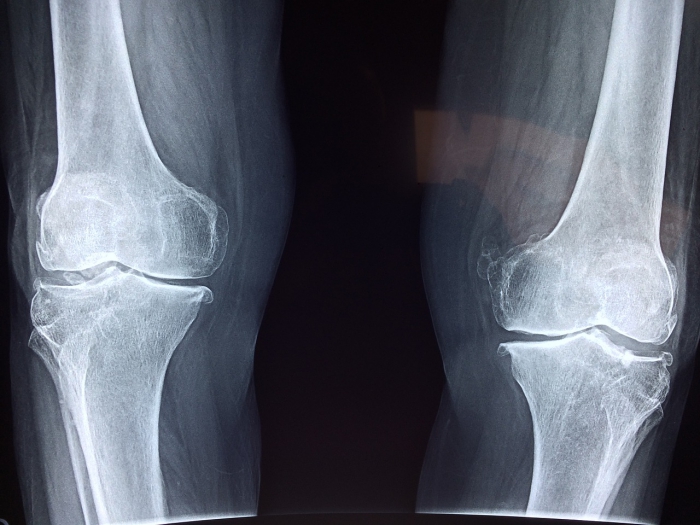

Training bei Knieschmerzen

Ca 15% der Untersuchungen sind Fehldiagnosen bei Knieschmerzen. Es könnten auch Krankheiten, wie Arthritis, Gicht oder Schuppenflechte Ursache sein.

Und in manchen Fällen hilft schon Training der Muskulatur und machen Operationen unnötig.